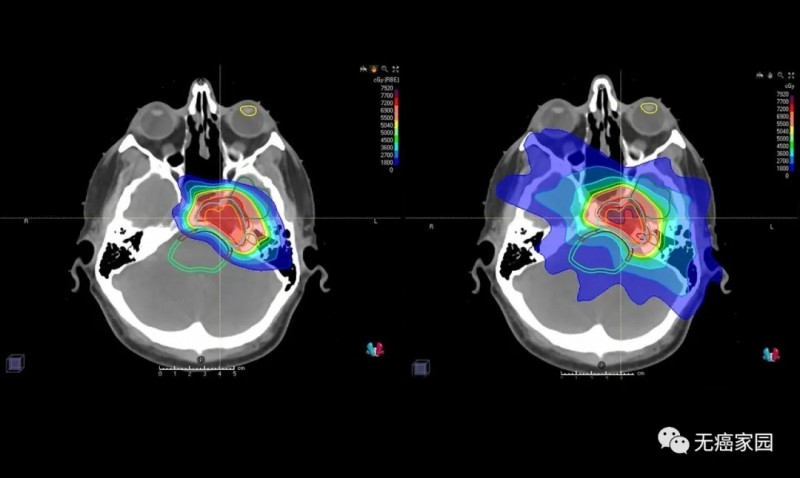

与传统形式的辐射相比,质子束会到达肿瘤内部的精准位置而不是沿着光束离开人体的路径释放大部分辐射剂量。实际上,质子没有肿瘤之外的辐射“退出剂量”,这意味着质子停在肿瘤上,不会继续伤害身体的健康部位。

图中患者的脑部扫描显示质子(左)如何专门针对肿瘤,而对周围组织和结构的辐射最小,传统的光子辐射(右)会损坏周围的组织和结构。